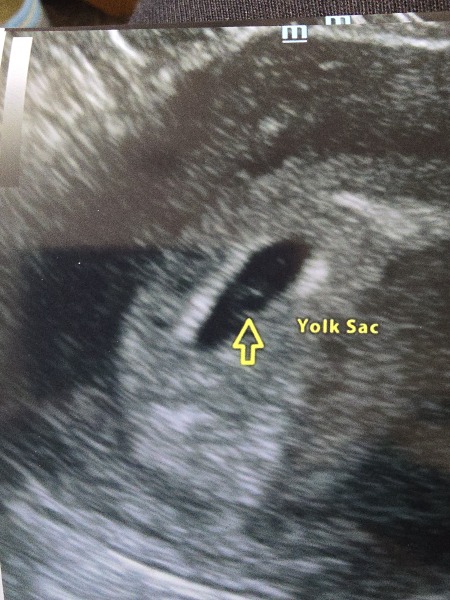

I’m 6+4 according to LMP but I’d predicted more like 6 weeks according to ovulation - I ovulate on day 19 rather than 14. A scan yesterday showed a gestational sac and a yolk sac but no fetal pole. So between 5-6 weeks? (Gestational sac measured 11.2mm which online searching seems to suggest 5+6 weeks). I’ve got to have a rescan. Am beside myself with worry as I had an early miscarriage last month and I’m convinced it’s going to happen again. Does anyone have any similar stories? Scan pic attached.

I went for a ultrasound at 6 weeks due to early previous miscarriages, panic struck and I ended up paying £75 but on scan measured 5 weeks and 5 days, does this ultrasound look normal, gs and yolk sack but no fetal pole, got to go back in 2 weeks for another ultrasound